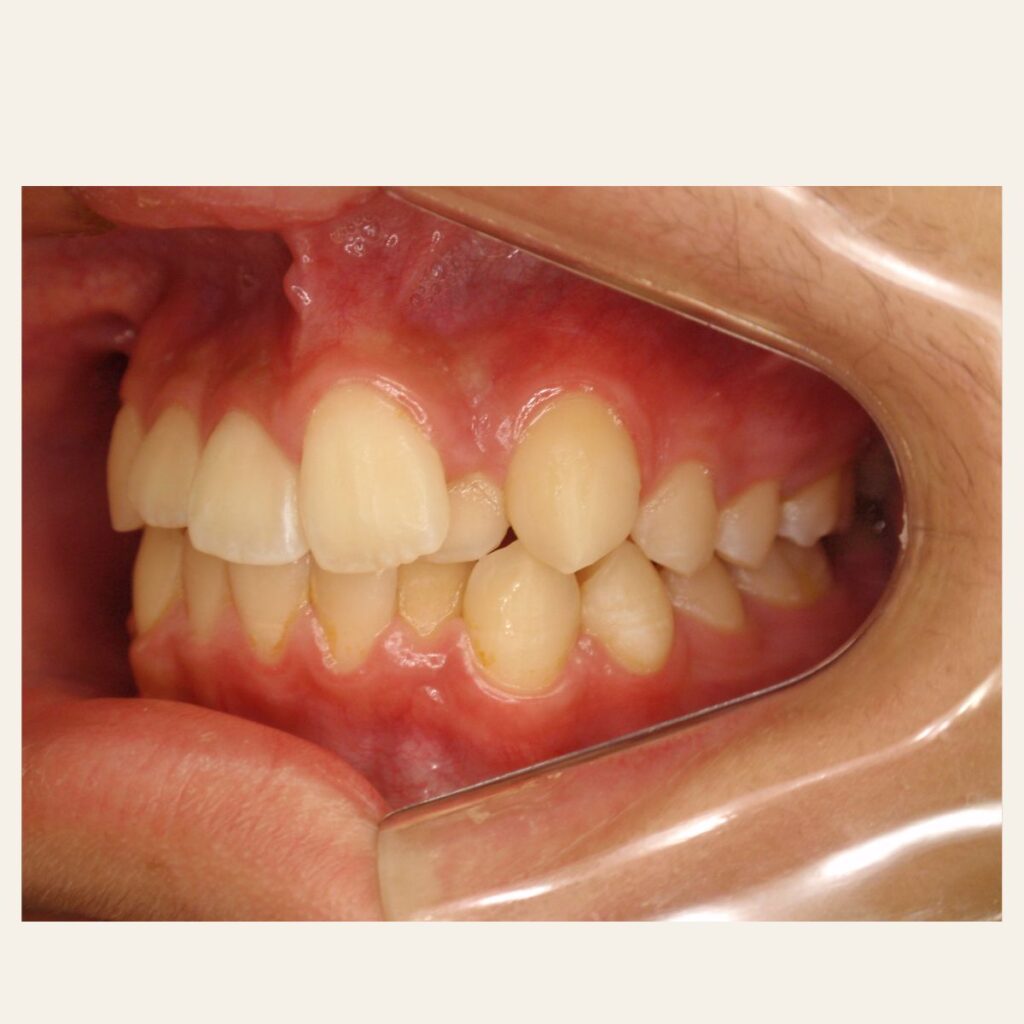

叢生の症例3(マウスピース矯正)

治療前後(BEFORE/AFTER)

| 年齢 | 10代女性、叢生、八重歯 |

| 主訴 | 八重歯、歯のガタガタ |

| 診断 | 叢生 |

| 治療方法 | 上下・マウスピース矯正(抜歯はしていません) |

| 治療期間 | 約2年 |

| 費用総額 | 1,100,000円(税込) |

| リスク・副作用 | 痛み/歯根吸収/歯肉退縮/後戻り など |

本症例では八重歯がかなり出ている叢生状態でした。

下顎前歯のガタガタも併せて治したいというご希望でした。

抜歯も検討しましたが、スキャナーによるシミュレーション、精密検査により歯列のスペースを確保しかみ合わせも意識しながら歯並びを整えるため、抜歯をしないで矯正治療を行いました。

思春期で難しいながらもマウスピース矯正で行い治療後は歯並びとかみ合わせが改善し、

見た目だけでなく歯磨きもしやすい状態になりました。